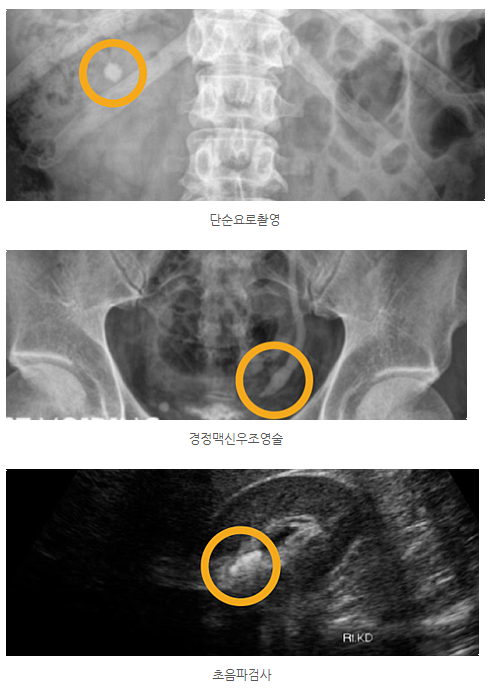

✅ 요로결석 진단 및 크기별 치료

정확한 상태 확인을 위해 소변 검사 및 단순 요로 촬영이나 초음파, 경정맥 신우 조영술 등을 활용해 결석의 정확한 위치를 파악합니다.